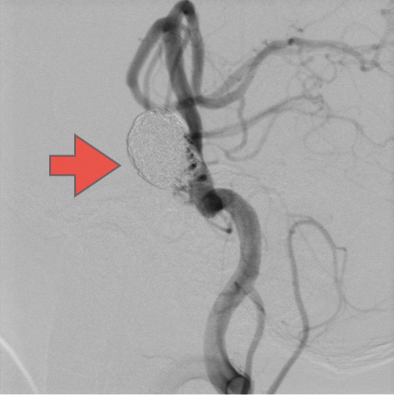

当科で治療した年々大きくなった大型脳底動脈瘤の3次元脳血管撮影像です。脳動脈瘤と周囲の血管の状態が非常によく分かるため、術前に十分な検討が可能でした。

術前

術後、脳底動脈瘤はコイルにより完全に塞栓され、正常の脳底動脈の血流は維持されている。